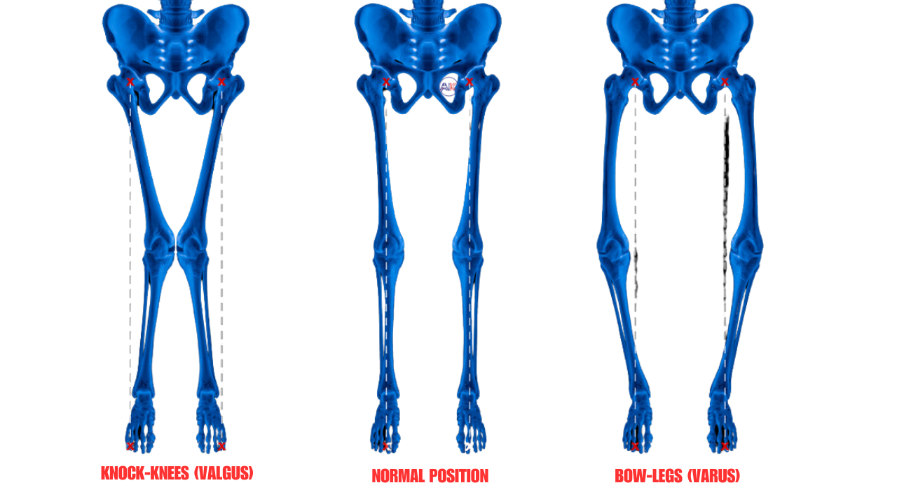

BOWLEGS OR KNOCK KNEES

These are structural abnormalities of the knee joint, where the legs are either bent outward (bowlegs) or inward (knock knees), potentially causing discomfort and gait issues.